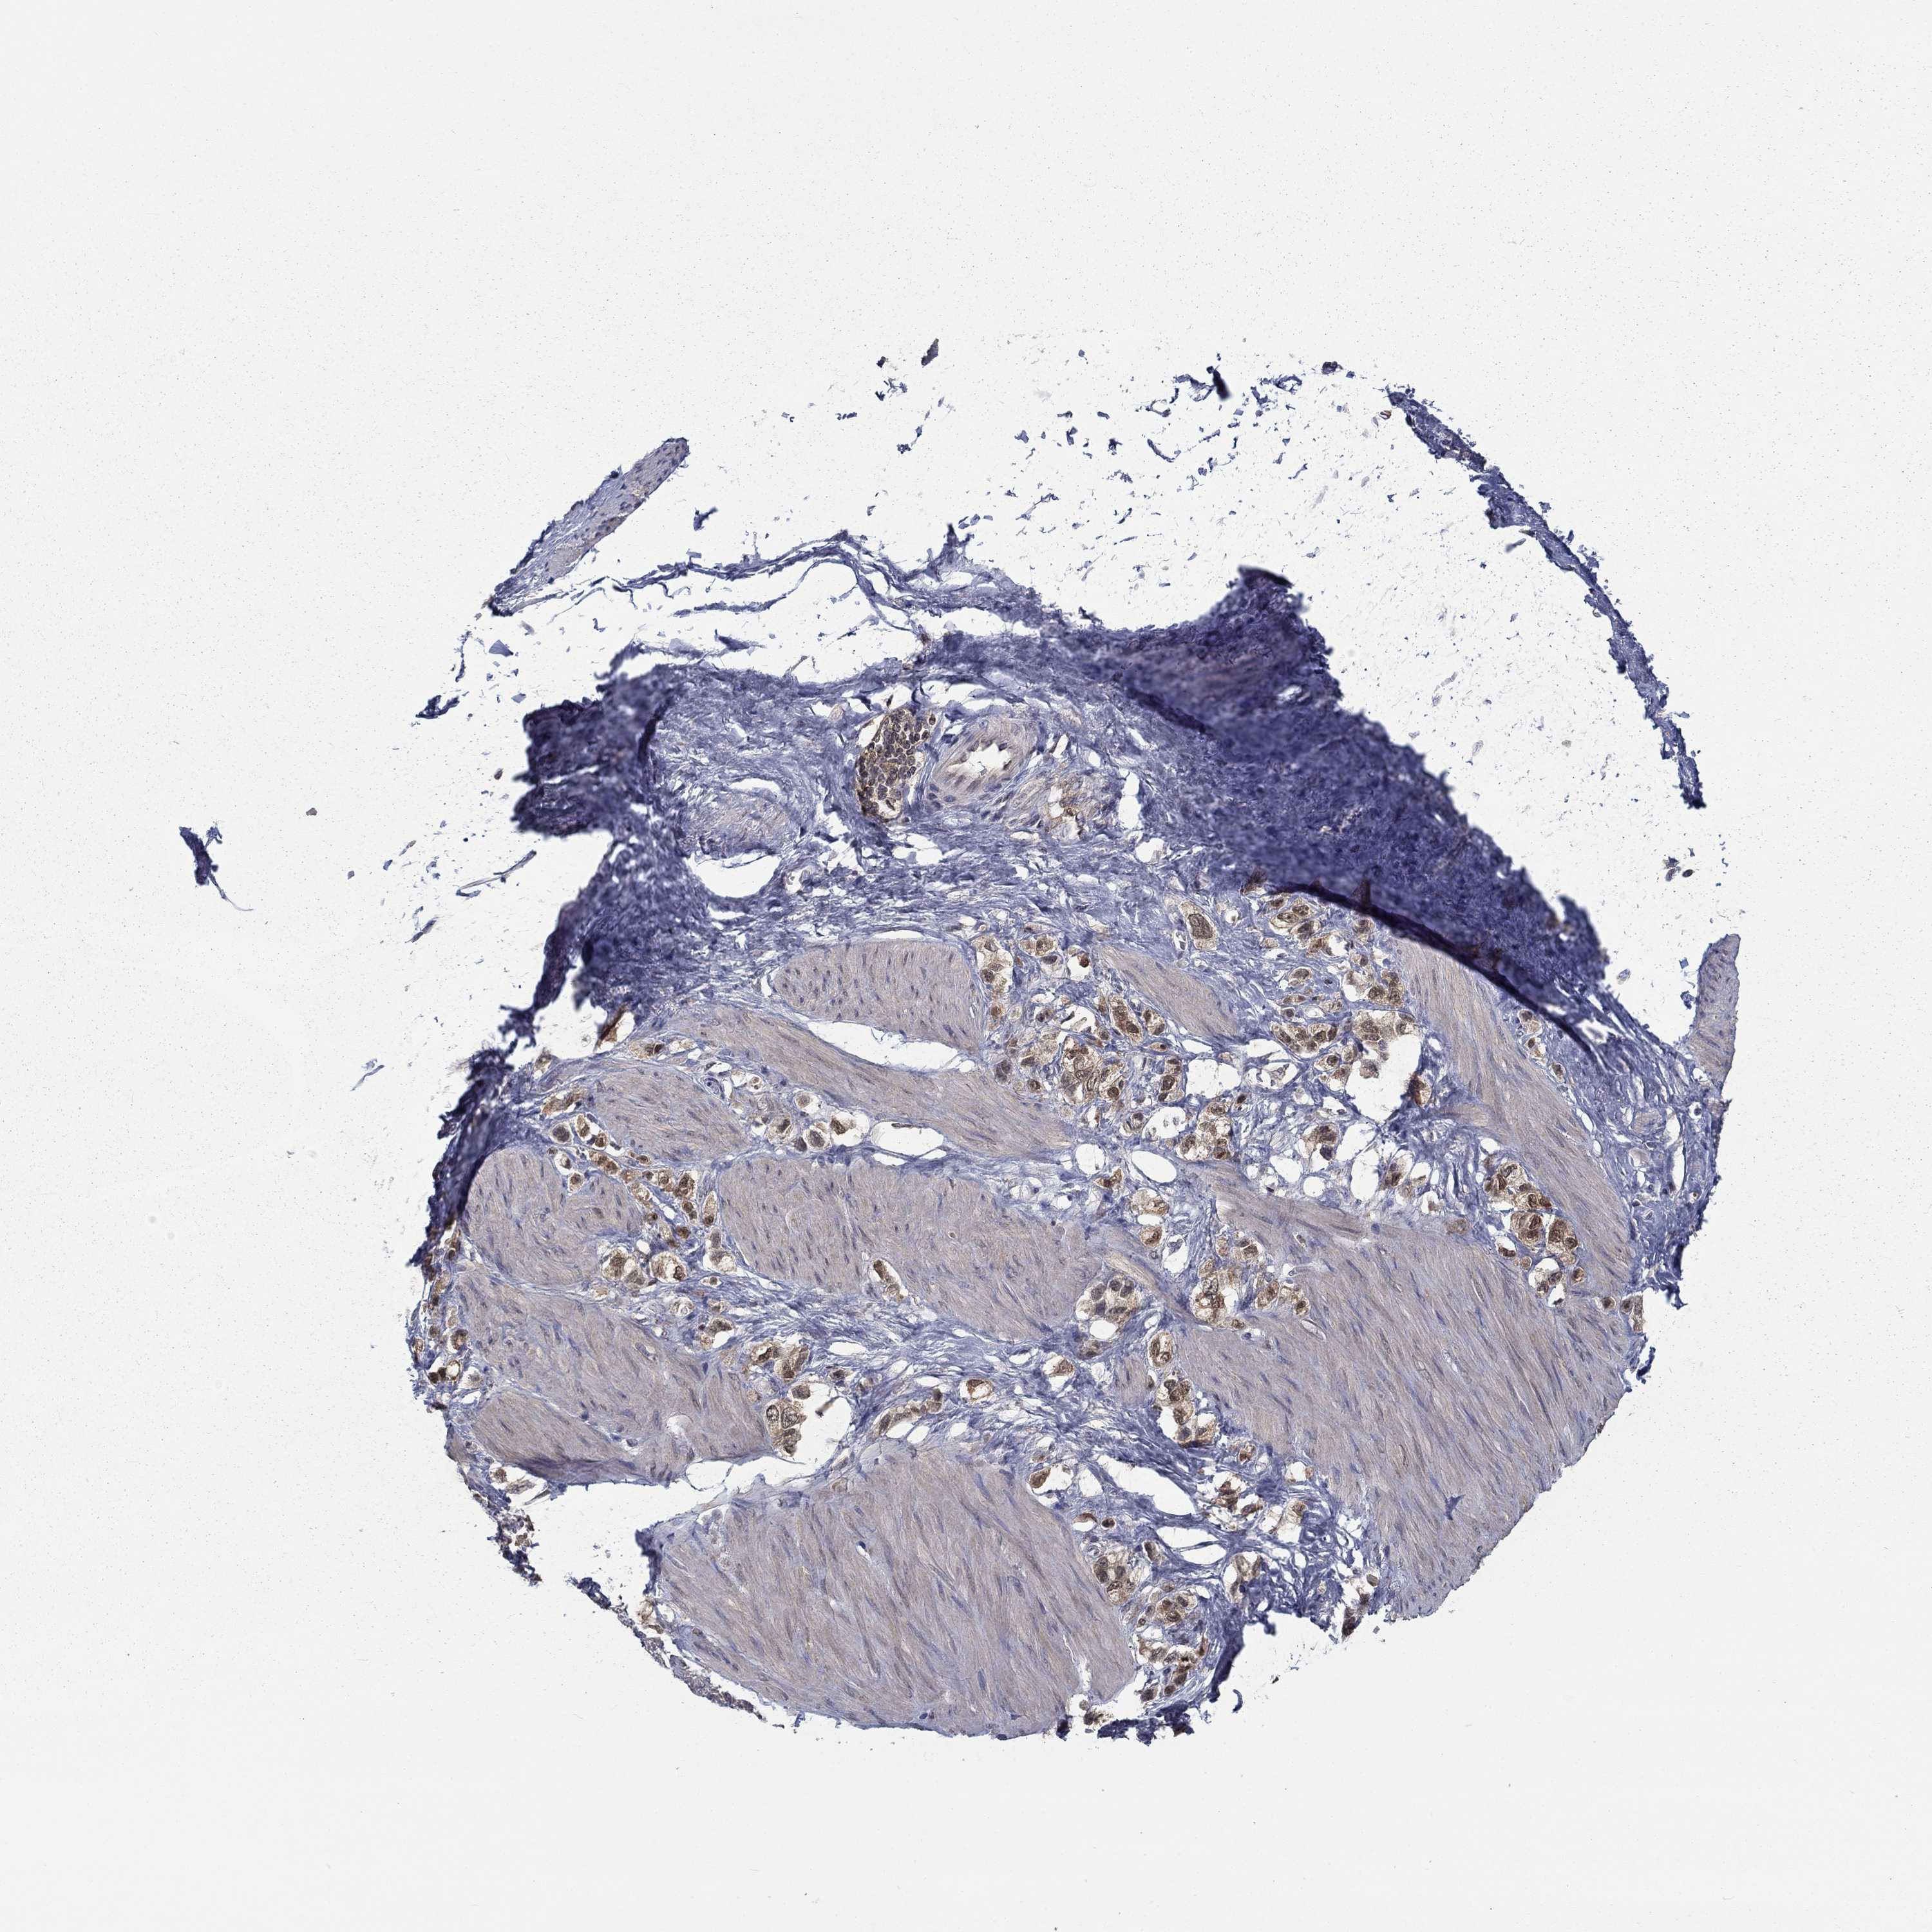

STOMACH CANCER - Protein expressioni

A mouse-over function shows sample information and annotation data. Click on an image to view it in a full screen mode. Samples can be filtered based on level of antibody staining by selecting one or several of the following categories: high, medium, low and not detected. The assay and annotation is described here.

Note that samples used for immunohistochemistry by the Human Protein Atlas do not correspond to samples in the TCGA dataset.

Antibody stainingi

Antibody staining in the annotated cell types in the current human tissue is reported as not detected, low, medium, or high, based on conventional immunohistochemistry profiling in selected tissues. This score is based on the combination of the staining intensity and fraction of stained cells.

Each image is clickable and will lead to virtual microscopy that enables deeper exploration of all samples and also displays staining intensity scores, fraction scores and subcellular localization as well as patient and tissue information for each sample.

Antibody HPA036999

Antibody HPA041289

Staining

High

Medium

Low

Not detected

Intensity

Strong

Moderate

Weak

Negative

Quantity

>75%

75%-25%

<25%

None

Location

Nuclear

Cytoplasmic/membranous

Cytoplasmic/membranous,nuclear

Adenocarcinoma, NOS

Adenocarcinoma, High grade